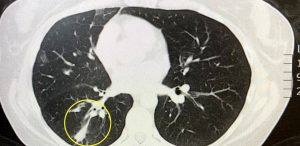

But after she began experiencing chest pains in September, she was sent for a series of scans which revealed a massive tumour growing on her lungs.

And following her first treatment in late October, Kate said the tumour on her lung had shrunk by 75 per cent – going from the size of an apple to the size of a grape – while there is zero traces of cancer in her lymph nodes & limited cancer in her liver.

After returning home from her first stint in Mexico in November, Kate underwent follow up scans at her local hospital in Australia – and claims doctors were shocked at her remarkable results, which revealed her tumour had reduced by 75% with zero traces of cancer in her lymph nodes.

Pictured is Kate’s scan in October 2018 And here it is pictured in March 2019,

Pictured is Kate’s scan in October 2018 And here it is pictured in March 2019,